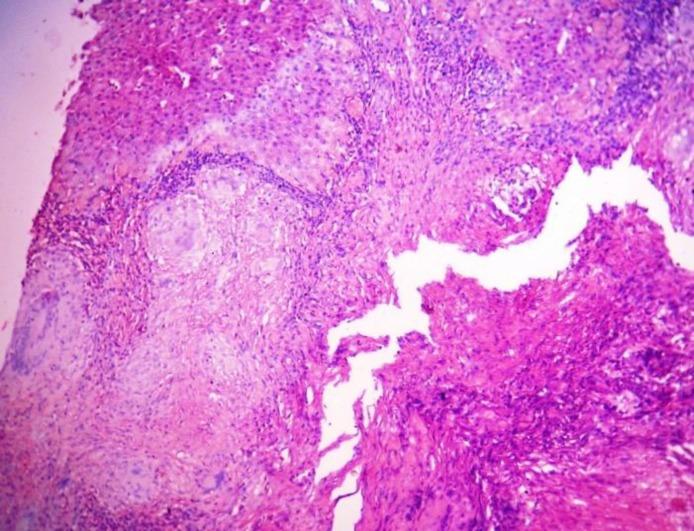

Isolated hepatic tuberculoma is localized hepatic tuberculosis (TB) without bile duct involvement, which presents as solitary or multiple nodular mass lesion of liver mimicking a neoplastic lesion in radiological evaluation. Clinical presentation and biochemical tests for liver functions show non-specific abnormality, which is not helpful for diagnosis. As the treatment, modality of isolated hepatic tuberculoma is anti-tubercular drugs. Prognosis is very good in comparison to other differential diagnoses. We are presenting such a rare case of isolated hepatic tuberculoma from tribal area of Bankura district, West Bengal, India in a 38-yr female patient presenting as fever, abdominal pain and solitary nodular lesion on radiological evaluation. Even different imaging modalities cannot make accurate diagnosis of isolated hepatic tuberculoma where simple biopsy and histopathology of the lesion can confirm the diagnosis.

孤立性肝结核瘤是局限于肝脏的结核病,不累及胆管,在影像学评估中表现为肝脏的单个或多个结节状肿块病变,类似肿瘤性病变。临床表现和肝功能生化检查显示非特异性异常,对诊断无帮助。作为治疗方法,孤立性肝结核瘤的治疗方式是抗结核药物。与其他鉴别诊断相比,预后非常好。我们在此呈现一例来自印度西孟加拉邦班库拉地区部落的罕见孤立性肝结核瘤病例,患者为一名38岁女性,表现为发热、腹痛,影像学评估显示为单个结节状病变。即使不同的影像学检查方法也无法对孤立性肝结核瘤做出准确诊断,而病变的简单活检和组织病理学检查可以确诊。